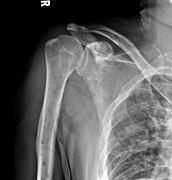

The diagnostic examination of a person with suspected multiple myeloma typically includes a skeletal survey. This is a series of X-rays of the skull, axial skeleton, and proximal long bones. Myeloma activity sometimes appears as "lytic lesions" (with local disappearance of normal bone due to resorption). And on the skull X-ray as "punched-out lesions" (pepper-pot skull). Lesions may also be sclerotic, which is seen as radiodense.[47] Overall, the radiodensity of myeloma is between −30 and 120 Hounsfield units (HU).[48] Magnetic resonance imaging is more sensitive than simple X-rays in the detection of lytic lesions, and may supersede a skeletal survey, especially when vertebral disease is suspected. Occasionally, a CT scan is performed to measure the size of soft-tissue plasmacytomas. Bone scans are typically not of any additional value in the workup of people with myeloma (no new bone formation; lytic lesions not well visualized on bone scan).

X-ray of the forearm, with lytic lesions

Humerus with multiple myeloma lesions

Same humerus before, with just subtle lesions